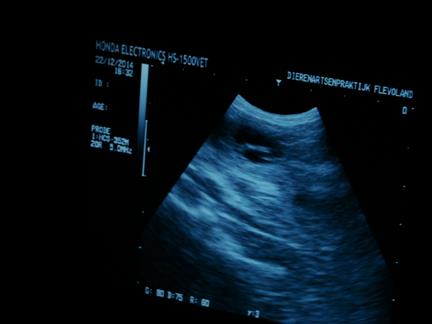

niet alle foto's zijn even duidelijk |

| maar in de donkere ronde vlekken |

zie je witte lijntjes |

| en dat zijn .......... de puppies :-) |

ook zijn de hartjes al aan het kloppen, allemaal prachtig om te zien |